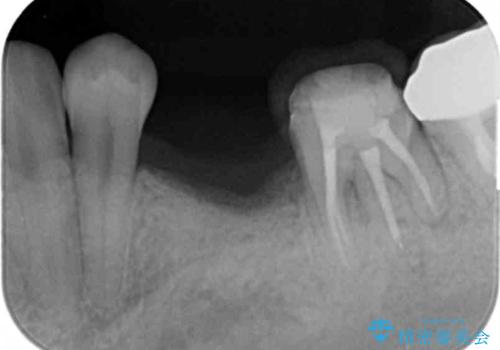

生まれつき永久歯の欠損がある場合、乳歯が大人になっても残っている場合があります。

残念ながらぐらつきが大きくなり、残すことが難しくなり抜去したのちインプラントを用いて咬合機能の回復をしっかりと行いました。